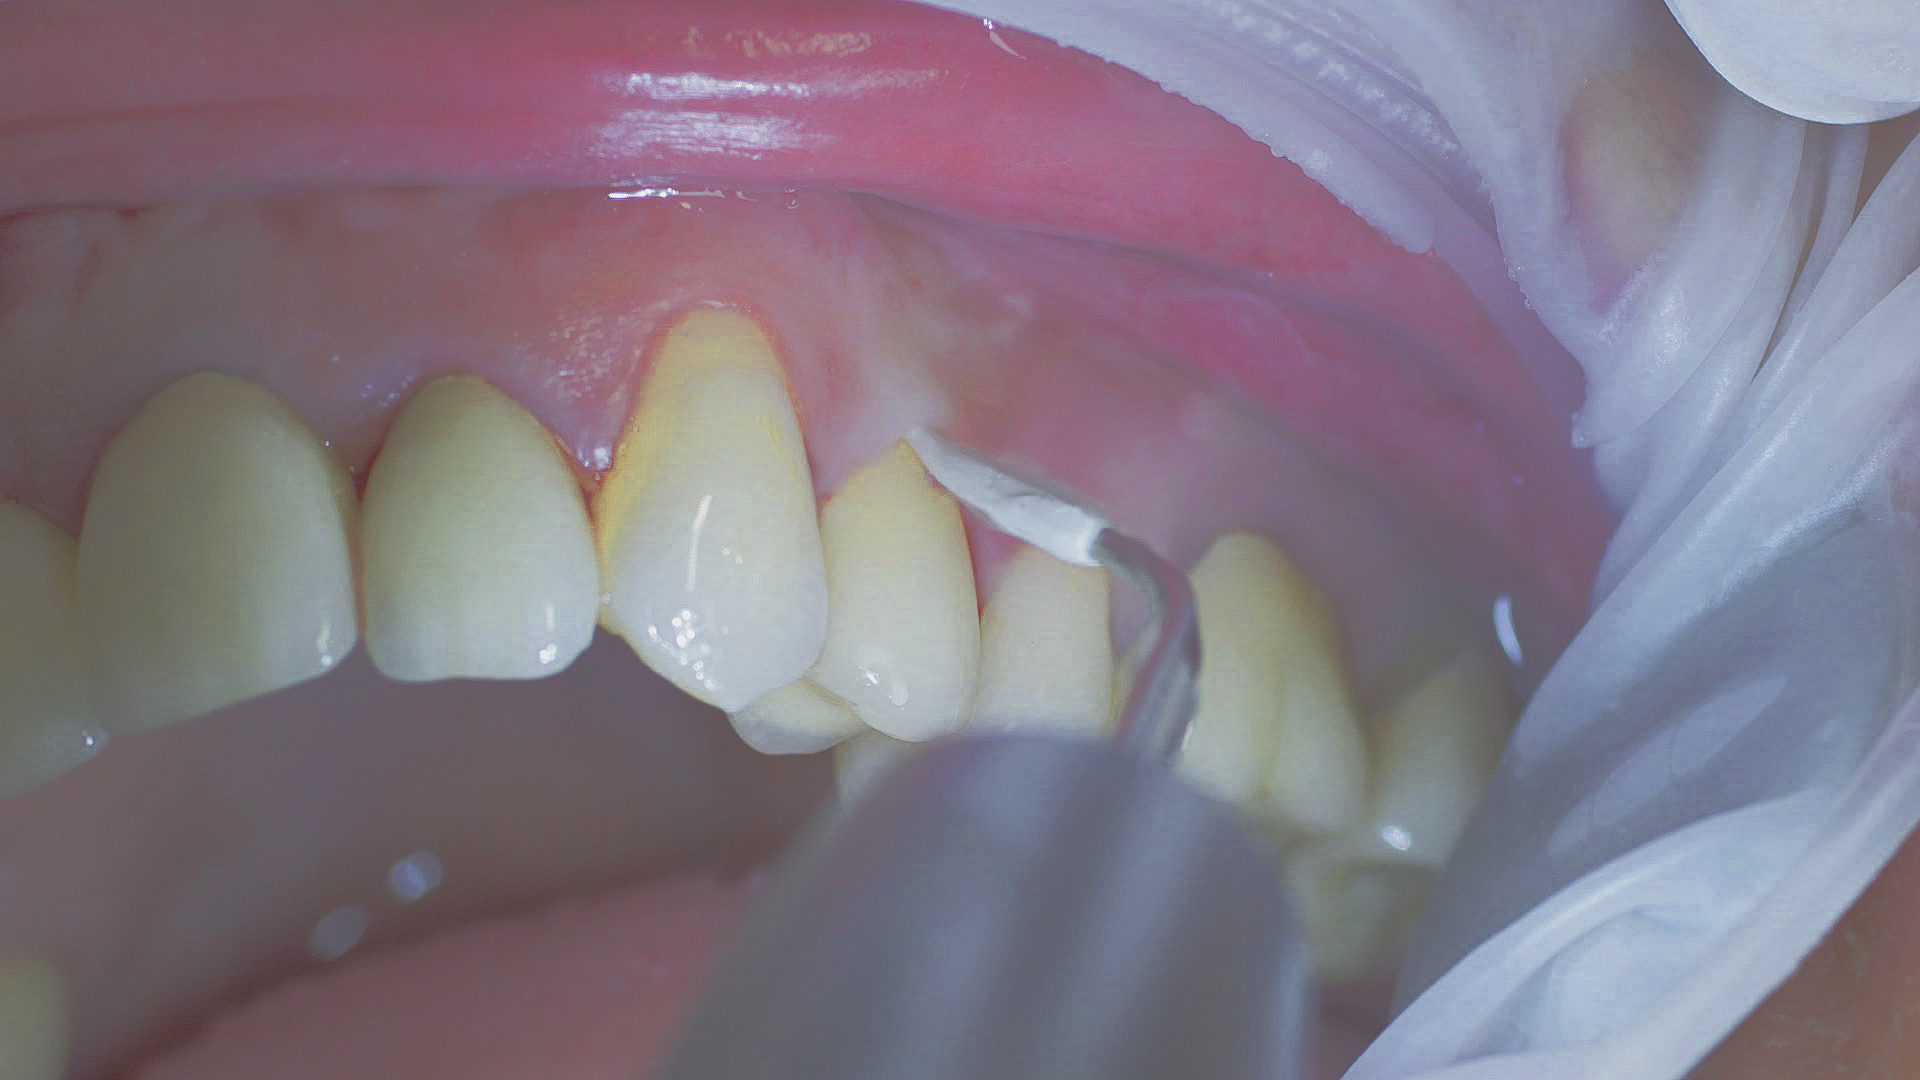

Dans les soins de suivi parodontal post-implantation, les concrétions molles (biofilm) et dures doivent être éliminées régulièrement par des techniques de nettoyage mécanique professionnelles. [16, 17] Dans les zones subgingivales et supragingivales, on utilise généralement pour cela des dispositifs à ultrasons (Fig. 4) en combinaison avec des instruments manuels si nécessaire.